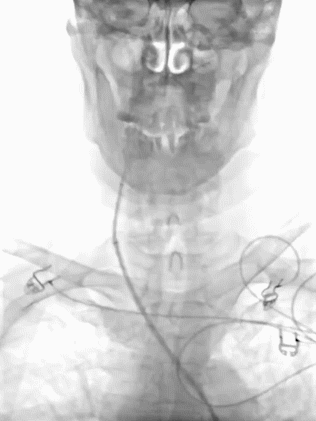

患者仰卧位,局部麻醉后,右侧腹股沟动脉穿刺插管,放置8F长鞘,将通桥大禹®球囊导引导管置于右侧颈内动脉,造影显示右侧大脑中动脉M2段闭塞,远端无显影。